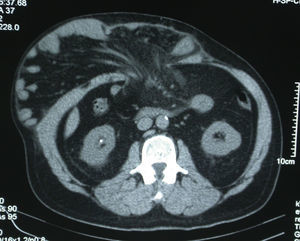

Se definió técnicamente una hernia o eventración abdominal con pérdida de domicilio como aquella en la cual más del 50% del contenido de la cavidad abdominal estuviera fuera de la misma (fig. 1). Esto fue determinado en casi todos los casos por la realización de una TAC abdominal preoperatoria (fig. 2). Una vez seleccionados los pacientes, se remitieron para valoración preanestésica y se programaron para ingreso hospitalario previo a la intervención quirúrgica.

Al cabo de 2 semanas de insuflación, se examinó la pared abdominal, evaluando la tensión que presentaba la musculatura en la parte lateral del abdomen, para constatar que esta se iba relajando adecuadamente. En algunos casos se realizó un control tomográfico del paciente (fig. 4), pero no de manera sistemática, ya que el seguimiento de la evolución fue principalmente clínico, considerando al paciente apto para la intervención cuando la musculatura lateral del abdomen se encontraba completamente distendida.